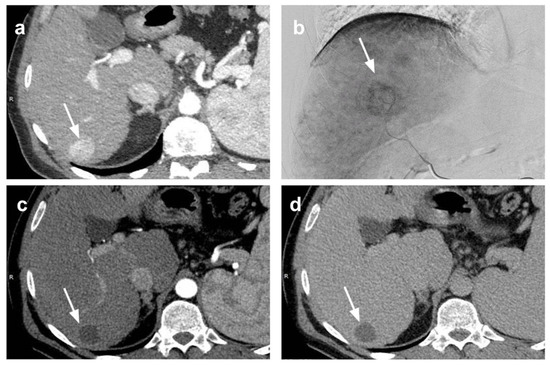

- Ibrahim, S.M.; Kulik, L.; Baker, T.; Ryu, R.K.; Mulcahy, M.F.; Abecassis, M.; Salem, R.; Lewandowski, R.J. Treating and Downstaging Hepatocellular Carcinoma in the Caudate Lobe with Yttrium-90 Radioembolization. Cardiovasc. Intervent. Radiol. 2012, 35, 1094–1101. [Google Scholar] [CrossRef]